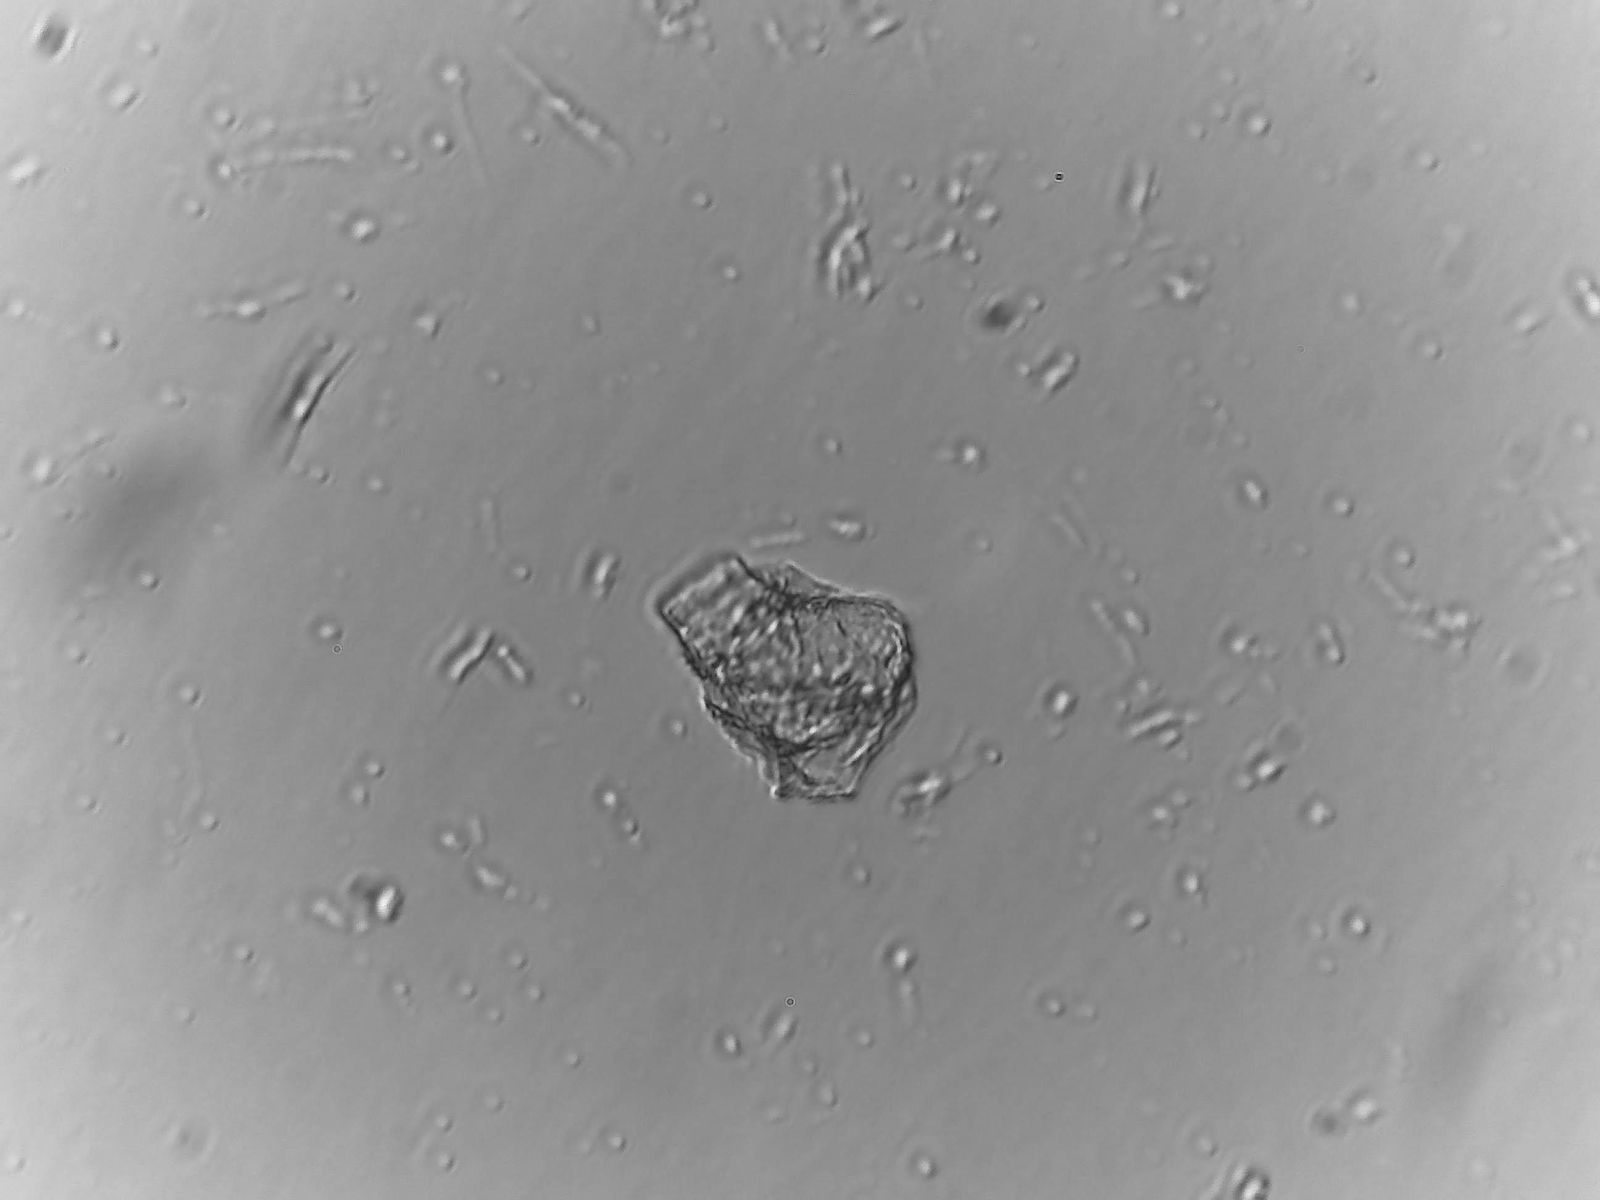

Das Ergebnis war erschreckend.

Ich habe Ihnen einige Bilder davon in den Anhang gelegt, was wir selbst "entdeckt" haben (kein Photoshop oder Fake!!)

Wir haben die Objektträger dann drei Tage liegen gelassen und wieder unter dem Mikroskop angesehen und mussten feststellen, dass sich neue Strukturen gebildet haben und die "alten" sich verändert haben.